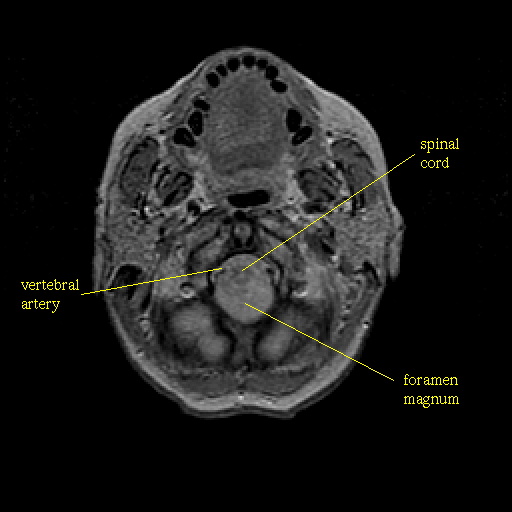

Proton density-weighted structural MR: Slice 4

Slice 4